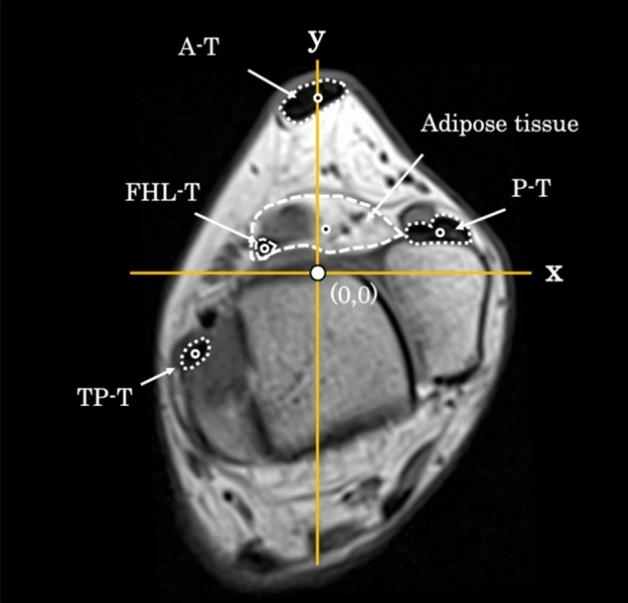

This study aimed to evaluate the presence of adipose tissue surrounding the flexor hallucis longus (FHL) tendon through gross dissection and magnetic resonance imaging (MRI). Grossly, we observed the FHL tendon and surrounding tissues in nine cadavers. Using MRI, we quantitatively evaluated each tissue from the horizontal plane in 40 healthy ankles. Macroscopic autopsy revealed the presence of adipose tissue behind the ankle joint between the FHL and fibula, and horizontal cross-sections showed an oval-shaped adipose tissue surrounding the tendon. The cross-sectional area on MRI was 14.4 mm (11.7-16.7) for the FHL tendon and 120.5 mm (100.3-149.4) for the adipose tissue. Additionally, the volume of the adipose tissue was 963.3 mm (896.2-1115.6). There is an adipose tissue around FHL tendon and maybe this close anatomical relationship might influence the function of the tendon and be involved in its pathologies.

本研究旨在通过大体解剖和磁共振成像(MRI)评估屈趾长肌腱(FHL)周围脂肪组织的存在。大体解剖观察了 9 具尸体的 FHL 肌腱和周围组织。使用 MRI,我们从 40 个健康踝关节的水平面对每个组织进行了定量评估。大体解剖发现,FHL 和腓骨之间的踝关节后面有脂肪组织,水平横切面显示肌腱周围有椭圆形脂肪组织。MRI 上 FHL 肌腱的横截面积为 14.4mm(11.7-16.7),脂肪组织的横截面积为 120.5mm(100.3-149.4)。此外,脂肪组织的体积为 963.3mm(896.2-1115.6)。FHL 肌腱周围有脂肪组织,这种紧密的解剖关系可能会影响肌腱的功能,并参与其病理过程。